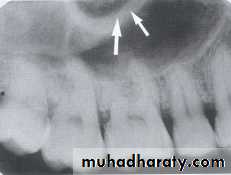

SEPTA WITHIN THE MAXILLARY SINUS:

Septa are bony wall that divided the maxillary sinus into compartment. Radiographically the septa appear as a radiopaque line within the sinus.

Nutrient Canals within Maxillary Sinus

Nutrient canals may be seen within maxillary sinuses. Nutrient canals are tiny, tubelike passageways through bone, which contain blood vessels and nerves that supply maxillary teeth and interdental areas. On a maxillary periapical image, a nutrient canal appears as a narrow radiolucent band bounded by two thin radiopaque lines.INVERTED Y